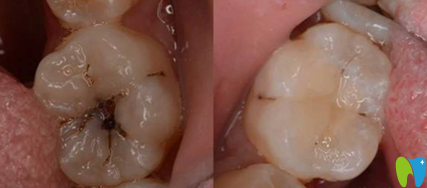

陳蔚蔚主任根管治療案例前后效果對比圖:

陳蔚蔚主任根管治療案例前后效果對比圖